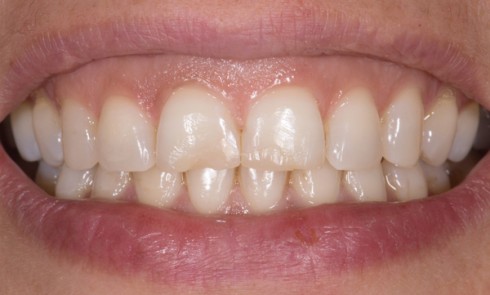

Article réservé à nos abonnés L’isolation dans le secteur antérieur

1. Préparation sous digue La mise en place de la digue dentaire dès cette étape permet un meilleur contrôle visuel...